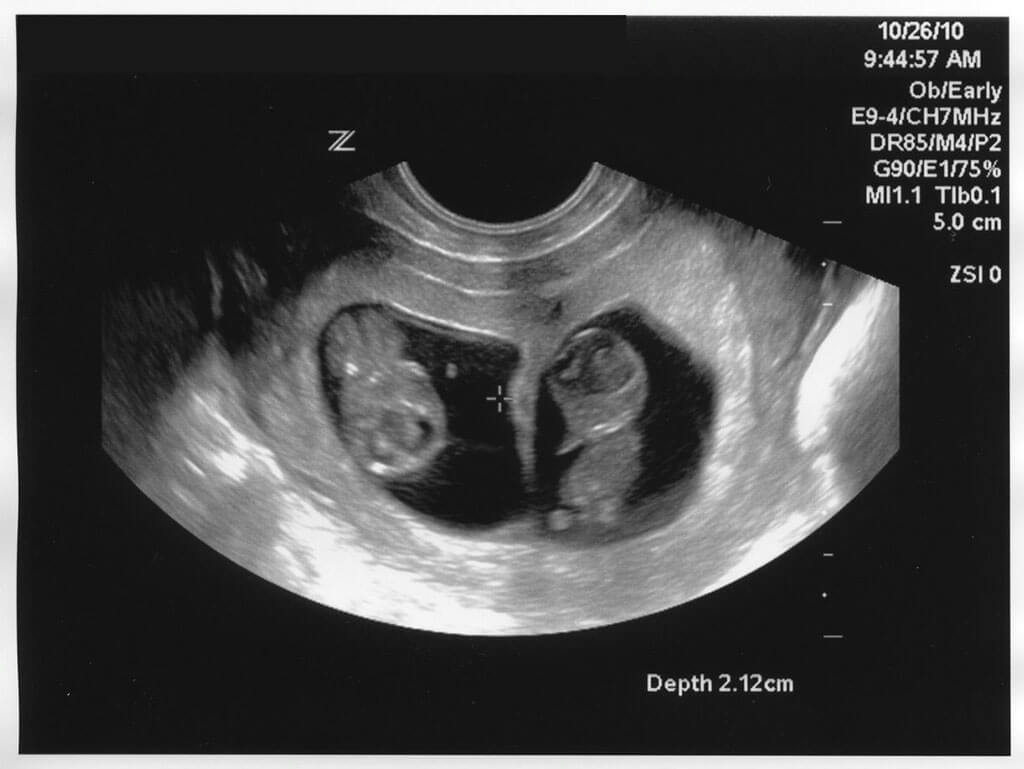

Building Their Dream Family Together

When Lianna got the news from the doctor, both families were over the moon. The second embryo had taken and Lianna would end up getting an ultrasound. The ultrasound would reveal the most stunning thing of all, Lianna was pregnant with twins! The announcement was as emotional and joyful as you could possibly imagine.